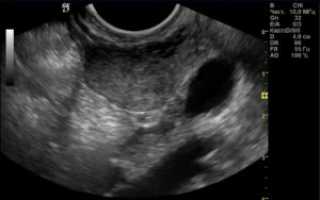

На женских форумах и медицинских порталах можно встретить множество историй о том, как медики перепутали на УЗИ у пациентки миому с беременностью. В пользу таких случаев можно привести только один факт: на ранних сроках плодное яйцо по своим размерам близко к миоматозной опухоли.

Так, на сроке в 5 недель плодное яйцо вырастает до 4-6 мм, к концу шестой недели – уже до 12-18 мм, и так далее. Миоматозные узлы делятся на маленькие – до 20 мм, средние 20-60 мм, и большие – свыше 60 мм. И если оборудование для УЗИ старое, снимки плохого качества, а доктор недостаточно компетентен, он может принять беременность за миому.

Но любой высококвалифицированный специалист никогда не позволит себе перепутать миоматозный узел и плодное яйцо. И дело не только в качестве снимков на УЗИ. Просто есть еще обычный осмотр и другие исследования, с помощью которых можно точно понять, беременность это или доброкачественная опухоль.

- В первую очередь диагностировать беременность позволит обычный гинекологический осмотр. Если пациентка ждет ребенка, матка обычно мягкой консистенции.

- Также доктор назначает дополнительные анализы крови и мочи, в частности гормональный анализ на ХГЧ. Миома матки никак не влияет на уровень хорионического гонадотропина, который является важнейшим показателем беременности. Поэтому даже обычный аптечный тест поможет дифференцировать опухоль от будущего материнства.

- Еще один показатель – менструальный цикл. Если у пациентки миома, то месячные сохраняются, иногда также появляются выделения в течение всего цикла. Для максимально точной диагностики доктор назначает специальное время для УЗИ – в первые 3-7 дней цикла.

В некоторых случаях беременность и миоматозная опухоль на УЗИ диагностируются одновременно, это происходит, когда размеры новообразования небольшие. Параметры опухоли измеряются в неделях, как и срок беременности. Считается, что зачать малыша можно при миоме размером меньше 12 недель, то есть меньше 10-11 см.